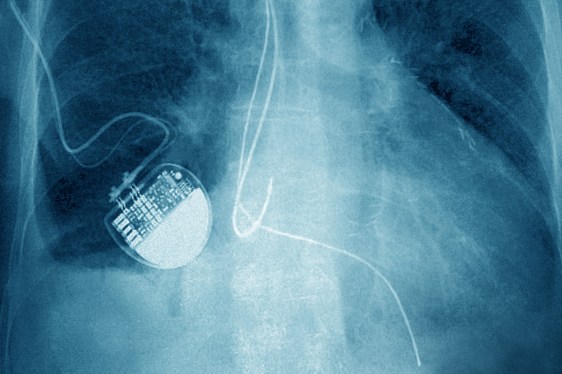

medical device